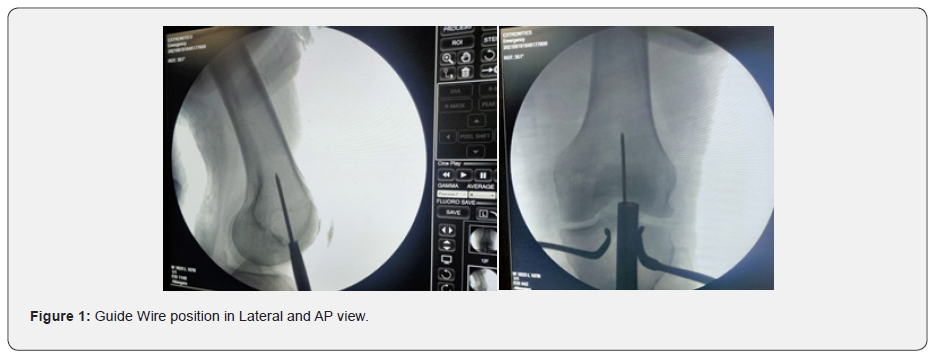

The present retrospective study was conducted in the Department of Orthopaedics, PGIMS Rohtak and included 10 cases aged between 20-70 years, who were operated for distal femoral shaft fractures over last 3 years with distal femoral nailing. Patients were retrospectively followed up with all their previous surgical records and radiographs. Patients were clinically examined, and functional outcomes were noted. Patients with age more than 70 years, having congenital or acquired deformity of injured limb before surgery, pathological fractures and open fractures were excluded from the study. Radiographs were taken in two planes, anteroposterior view, and lateral view before planning for surgical fixation for distal femur fractures. Patients were laid supine withaffectedknee placed in ~30° flexion over operating table with a bolster underneath the knee. Knee flexion prevents distal fragment from being pulled into more flexion by gastrocnemius. Inferior pole of patella and borders of patella tendon were marked. A2cm incision was made from inferior pole of patella distal through tendon. We used aTranstendinous approach. Tenotomy was done to develop paratenon layer, sharp dissection through paratenon and then patellar tendon was done. Guide pin start point was in centre of intercondylar notch on anteroposterior view and just superior to Blumensaat’s line on lateral view (Figure 1).